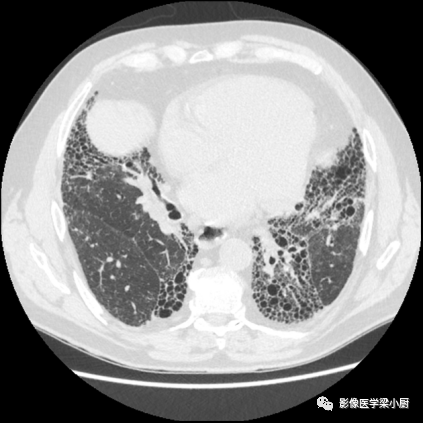

3.蜂窝:呈镞状囊性低密度影,囊壁光整,厚度1~3mm,直径常为3~10mm,偶尔可达2.5cm。蜂窝是HRCT的UIP型最具特征性的表现,蜂窝影预测UIP的灵敏度和特异度较高。

蜂窝的组成目前尚不清楚,推测为扩张的小气道,是纤维化进展的标志,提示预后差。

双肺呈弥漫蜂窝状改变